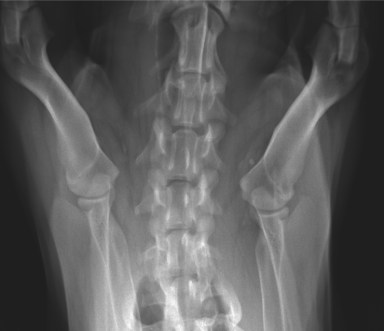

RadioQuiz 8

Signalement: Berger allemand, femelle stérilisée, 10 ans.

Histoire clinique: Boiterie et douleur à la palpation du coude gauche.

Cliquez sur l’image pour un affichage plein écran.

Pour la réponse, cliquez ICI.